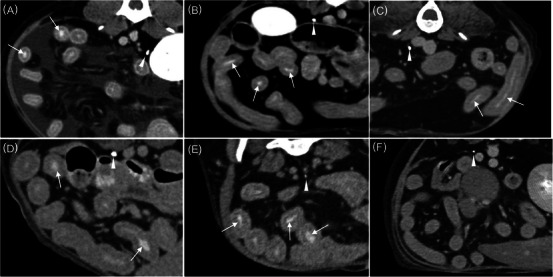

The intestinal vicarious contrast medium excretion (VCME) can occur in dogs with protein-losing enteropathy (PLE), and studies for intestinal VCME in dogs are lacking. This retrospective case-control study aimed to assess whether intestinal VCME could be observed on delayed CT in dogs with and without PLE. Thirty dogs who underwent abdominal delayed CT in the 10 min-delayed phase following the injection of contrast medium were enrolled. Six dogs were classified into the group with enteropathy based on imaging findings or abnormal results from cytology or histology. The six dogs had concurrent hypoalbuminemia and were diagnosed with presumed PLE. Five of the six dogs in the group with enteropathy had intestinal VCME. In the 24 dogs of the group without enteropathy, intestinal VCME was not detected on delayed CT, and VCME to the cisterna chyli was observed in one dog. The frequency of intestinal VCME was significantly higher in the group with enteropathy than in the group without enteropathy (p < .001). The presence of intestinal VCME on the delayed CT can be observed in dogs with PLE, and it can be used as noninvasive additional supportive evidence of canine PLE prior to histopathologic evaluation.

Abstract Image